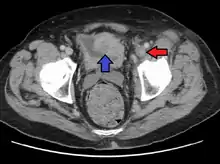

Phlegmasia cerulea dolens (literally: painful blue inflammation) is an uncommon severe form of deep venous thrombosis which results from extensive thrombotic occlusion (blockage by a thrombus) of the major and the collateral veins of an extremity.[1][2] It is characterized by sudden severe pain, swelling, cyanosis and edema of the affected limb. There is a high risk of massive pulmonary embolism, even under anticoagulation. Foot gangrene may also occur. An underlying malignancy is found in 50% of cases. Usually, it occurs in those afflicted by a life-threatening illness.[1]

| A person with a two hour history of phlegmasia cerulea dolens (left leg, right side of image) |